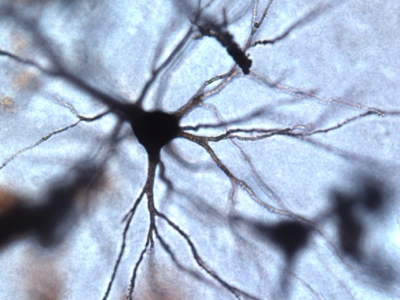

No 23 | La réaction noire (la reazione nera)